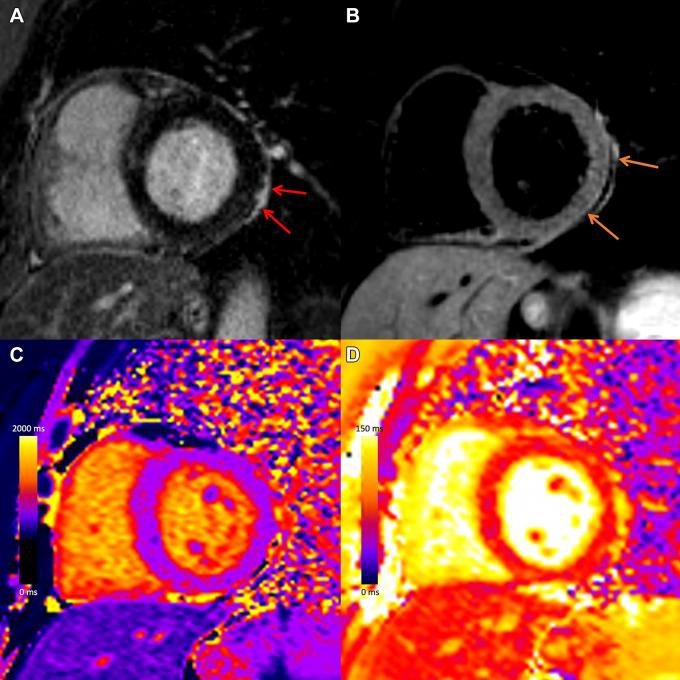

Myocarditis is a nonischemic inflammatory disease of the myocardium that can be triggered by a multitude of events, including viral infection and toxins. Recently, there has been heightened interest in myocarditis given its association with COVID-19 vaccination. Timely identification of myocarditis can affect patient management and prognosis. Therefore, it is crucial for radiologists and cardiac imagers to understand the role of cardiac imaging to establish a diagnosis and inform treatment decisions. Cardiac MRI is the most important noninvasive imaging modality for evaluation of myocarditis, with typical findings of focal or diffuse myocardial edema and myocardial damage, including presence of late gadolinium enhancement. There are currently limited data available to indicate that the pattern of myocardial injury following COVID-19 vaccination is similar to other causes of myocarditis, although the severity of disease may be relatively mild. A description of the role of imaging and typical imaging features will be reviewed here, with a focus on emerging data in the setting of myocarditis after COVID-19 vaccination. MRI, Heart, Inflammation © RSNA, 2021.

心肌炎是一种心肌的非缺血性炎症性疾病,可由多种因素引发,包括病毒感染和毒素。近来,鉴于心肌炎与新冠病毒疫苗接种之间的关联,人们对其兴趣大增。及时识别心肌炎会影响患者的管理和预后。因此,放射科医生和心脏影像专家了解心脏成像在确立诊断及指导治疗决策方面的作用至关重要。心脏磁共振成像(MRI)是评估心肌炎最重要的非侵入性成像方式,其典型表现为局灶性或弥漫性心肌水肿以及心肌损伤,包括钆剂延迟强化的存在。目前仅有有限的数据表明,新冠病毒疫苗接种后心肌损伤的模式与心肌炎的其他病因相似,不过疾病的严重程度可能相对较轻。本文将回顾成像的作用及典型成像特征,重点关注新冠病毒疫苗接种后心肌炎相关的新出现数据。MRI、心脏、炎症 © RSNA,2021年